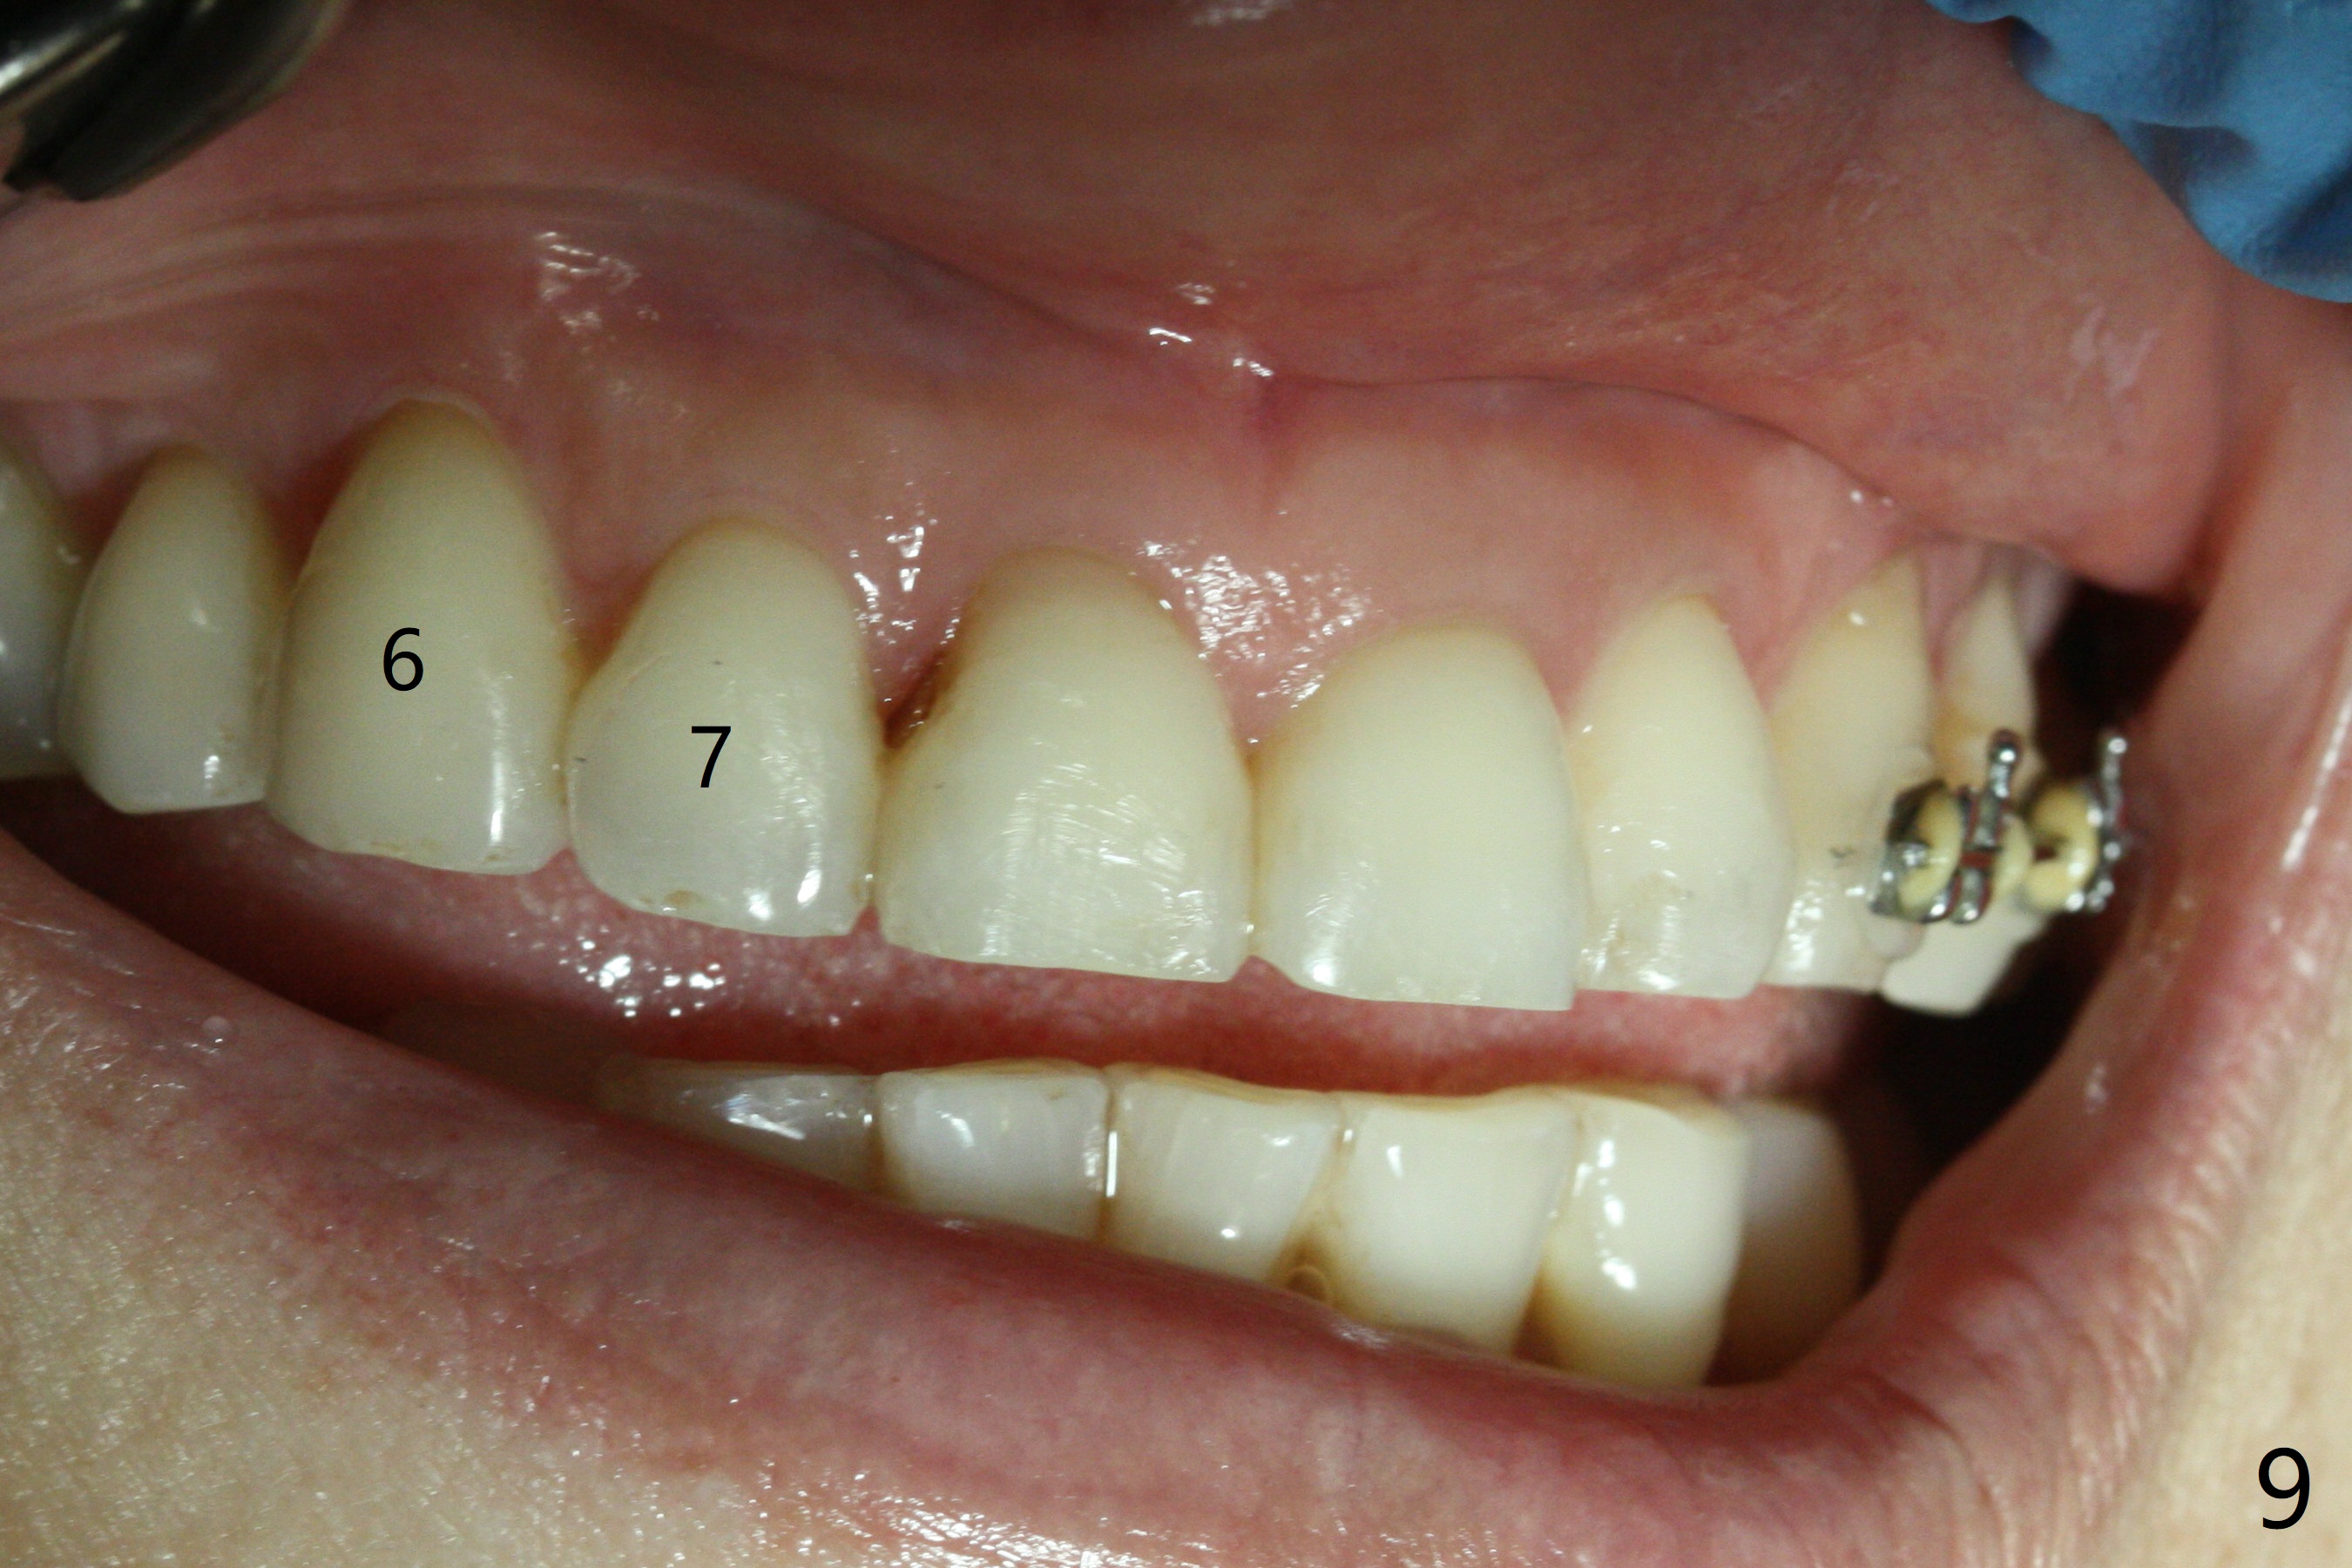

Seven months of orthodontic treatment and 2 months post implant placement, the edentulous mesiodistal space appears to return normal, but the implant has pain when the healing abutment is retightened (Fig.8). Since the patient is going to return home country for reunion, the last two anterior brackets at #6 and 7 are remove and the arch wire is shortened for cosmetics (Fig.9).